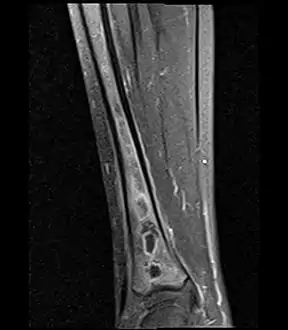

A Brodie abscess is a subacute osteomyelitis, which may persist for years before progressing to a chronic, frank osteomyelitis. Classically, this may present after progression to a draining abscess extending from the tibia out through the skin. Occasionally acute osteomyelitis may be contained to a localized area and walled off by fibrous and granulation tissue.

Oval, elliptical, or serpentine radiolucency usually greater than 1 cm surrounded by a heavily reactive sclerosis, granulation tissue, and a nidus often less than 1 cm. The margins often appear scalloped on radiograph. Brodie's abscess is best visualized using computed tomography (CT) scan. Associated atrophy of soft tissue near the site of infection and shortening of the affected bone. Osteoblastoma may be a classic sign for Brodie's abscess.